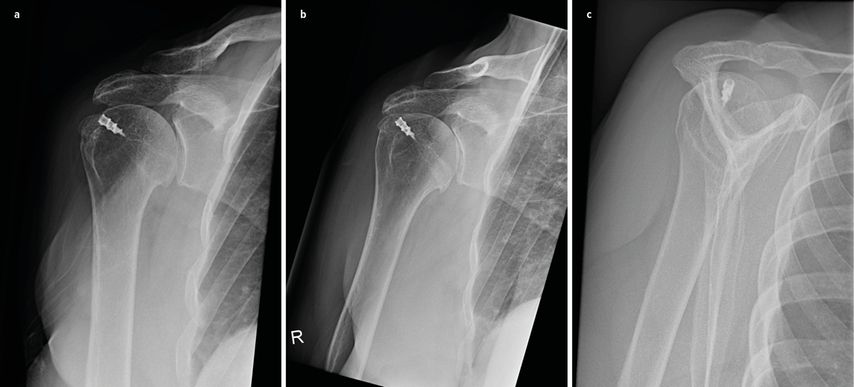

Abb. 1:Röntgen in 2 Ebenen und CT einer Reruptur mit disloziertem Anker und intraoperativer arthroskopischer Implantatentfernung

Röntgenaufnahmen: Standardmäßig werden Röntgenaufnahmen der Schulter in drei Ebenen angefertigt, um den knöchernen Zustand, die Gelenkskongruenz sowie das Vorhandensein und die Position des Implantats zu bewerten.

Eine Erweiterung erfolgt gegebenenfalls per Computertomografie (CT) oder CT-Arthrografie.